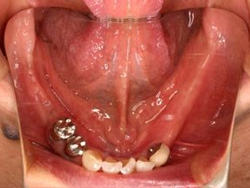

術前(下顎粘膜面、鏡像)